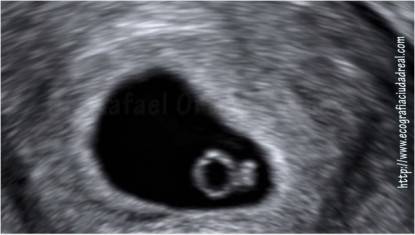

Il sacco vitellino è una struttura tondeggiante ed è il primo elemento visibile nel sacco gestazionale durante la gravidanza, di solito intorno alle 5 settimane di gestazione. La sua funzione è quella di nutrire l’embrione e cresce di 1 mm alla settimana fino alla decima/dodicesima settimana, raggiungendo tra i 5 e i 7 mm e poi regredisce, lasciando il suo ruolo alla placenta.

sacco vitellinoAnatomicamente ha una forma a pera e comunica con il tubo digestivo attraverso il tubo vitellino.

Nel video che segue vedrete il sacco vitellino non solo come appare nelle classiche ecografie in 2D, ma anche come è davvero, grazie alle immagini delle ecografie in 3 e 4D.